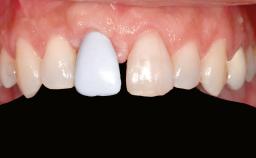

A 56-year-old woman presented for treatment with complete edentulism of the maxilla. She had been using a complete removable denture since she was relatively young (age 30). Her chief complaint at presentation was lack of retention of the upper denture and a desire for a better restoration in order to improve retention, function, and esthetics. An initial clinical examination showed that the anterior maxilla was moderately atrophic both horizontally and vertically, also revealing a vertical deficiency of the posterior alveolar process. The mandible included natural teeth from 45 to 35, with previous extrusion of the anterior teeth that was being orthodontically treated. Also, there were two external hexagon dental implants at sites 46 and 36 that had been inserted elsewhere at a previous point in time. As the conditions in the mandible were healthy, including the teeth and the two implants, the patient had no complaints there.